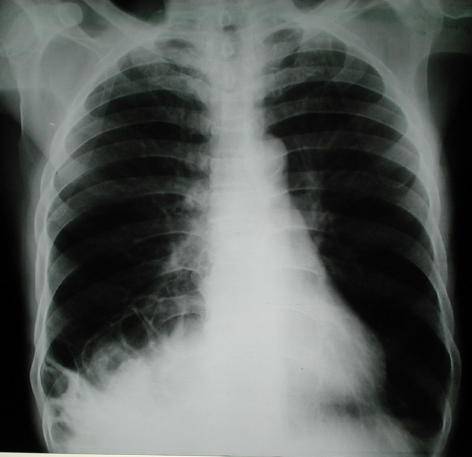

Rx Torax Posteroanterior reciente Estudio Radiológico del torax actual, pre operatorio

Radiología del tórax:

También puede observarse la hiperplasia compensatoria del pulmón Izquierdo.